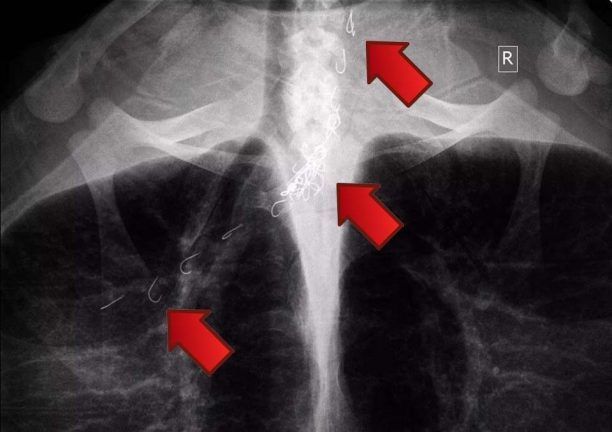

Στο Κέντρο Διάσωσης που λειτουργεί ο σύλλογος «ΑΡΧΕΛΩΝ» στη Γλυφάδα Αττικής βρίσκεται από τις 2 Οκτωβρίου η θαλάσσια χελώνα Caretta – caretta η οποία εντοπίστηκε στη περιοχή της Αγίας Άννας στο νησί της Νάξου να κολυμπάει έχοντας καταπιεί αγκίστρια.

Δύο μέλη του Συλλόγου Προστασία Άγριας Ζωής Νάξου που είδαν τις πετονιές να κρέμονται από το στόμα και να έχουν μπλεχτεί στο πτερύγιο της κατάφεραν με κόπο να τη βγάλουν στην στεριά και να τη στείλουν στη συνέχεια στον σύλλογο «ΑΡΧΕΛΩΝ» για περίθαλψη.

Η ακτινογραφία - που δημοσιεύουμε - έδειξε ότι τα αγκίστρια τα οποία κατάπιε η χελώνα βρίσκονται στον οισοφάγο αλλά έχουν προχωρήσει μέχρι τον πνεύμονα της εξήγησε στο www.zoosos.gr o Γιάννης Ορφανός εκ μέρους του Συλλόγου Προστασία Άγριας Ζωής Νάξου.

Πρόκειται για μια εξαιρετικά δύσκολη περίπτωση και οι επιστήμονες αναζητούν λύση για να τα αφαιρέσουν από το κορμί του θαλάσσιου ερπετού. Τα αγκίστρια και τα αλιευτικά εργαλεία κάθε είδους αποτελούν θανάσιμο κίνδυνο για τα ζώα της στεριάς και τη θάλασσας.